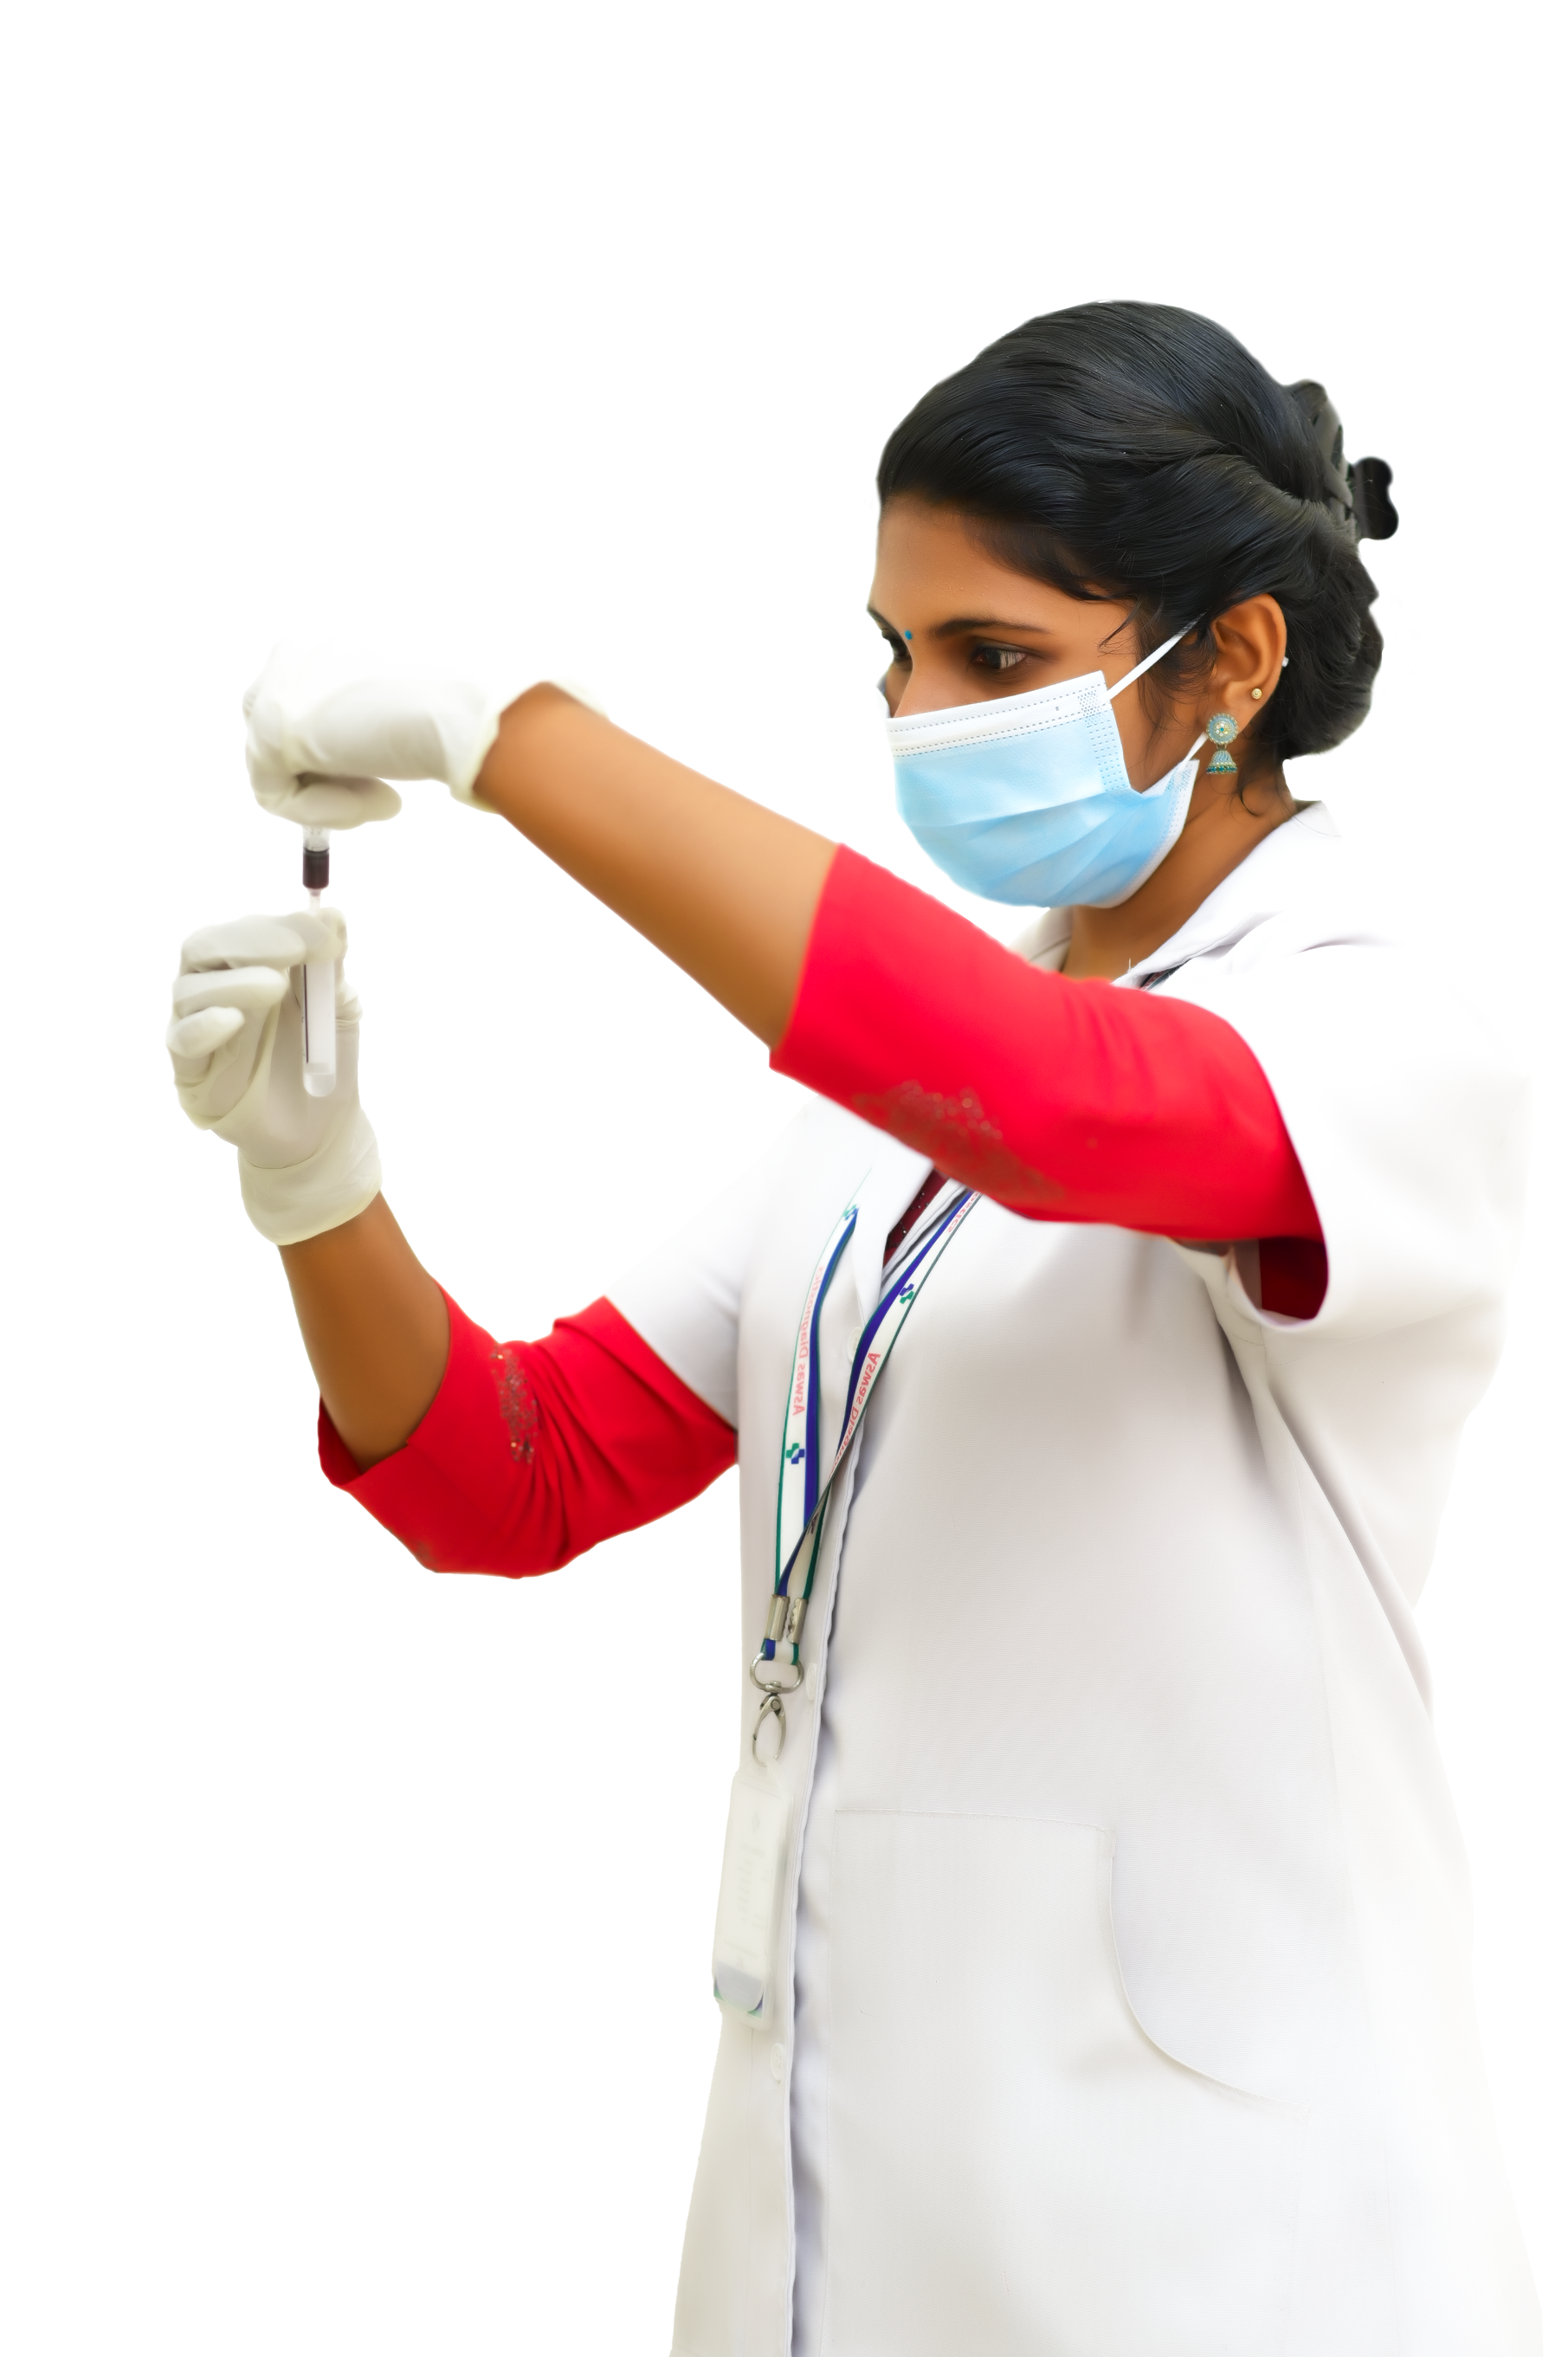

Behind every accurate diagnosis lies the expertise of our qualified lab technicians. Equipped with extensive knowledge and experience, our skilled technicians perform tests with utmost precision and attention to detail.

We firmly believe in the power of early detection to safeguard your well-being. Our wide range of Clinical & Preventive Tests enables us to identify potential health issues at their nascent stages, facilitating prompt intervention and preventive measures.

we prioritize your well-being by providing expert medical care tailored to your specific needs. Our highly qualified and experienced doctors are committed to offering personalized attention and treatment plans, ensuring that you receive the best care possible.